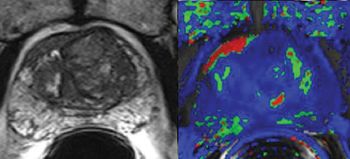

Washington University’s Mallinckrodt Institute of Radiology is imaging cervical cancer patients with hybrid PET/MR. Here’s what they’ve learned about this new modality.

Osman Ratib, MD, PhD, FAHA, professor and chief of nuclear medicine in the Department of Radiology at the University Hospital of Geneva, discusses the advantages and future of the hybrid PET/MR modality.